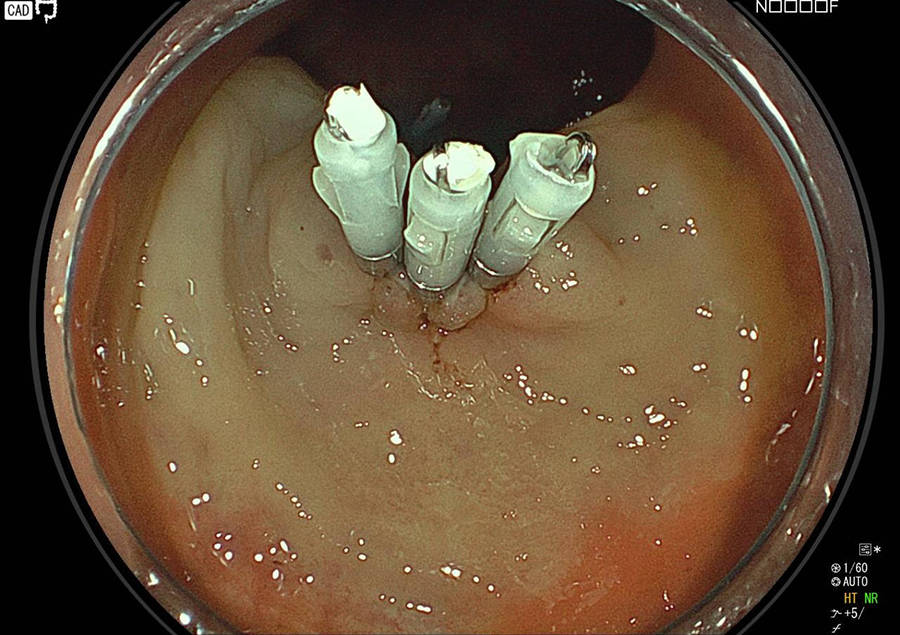

検査の様子

そこで当院では大腸カメラ検査時にポリープや早期がんが発見された場合は、可能な限り積極的にその場で切除しております。

ポリープを切除する時、あるいは切除の数日後に出血することがまれにあり、 出血が多い場合には入院して治療を受けていただくこともあります。

②穿孔

腸の壁の厚さは5㎜しかないので、切除した時に腸に穴を開けてしまう可能性もごくまれに(0.1~0.01%)あります。

大量出血、穿孔の場合には再度内視鏡処置を行ったり、開腹手術をすることで治療いたします。